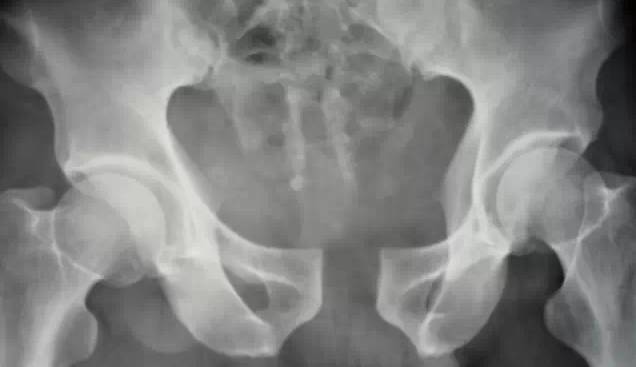

X线片可见耻骨联合间距离明显增宽,超过5mm,有的可达10~15mm,并有上下错位现象。慢性者可见联合之关节面毛躁不平、增生等。